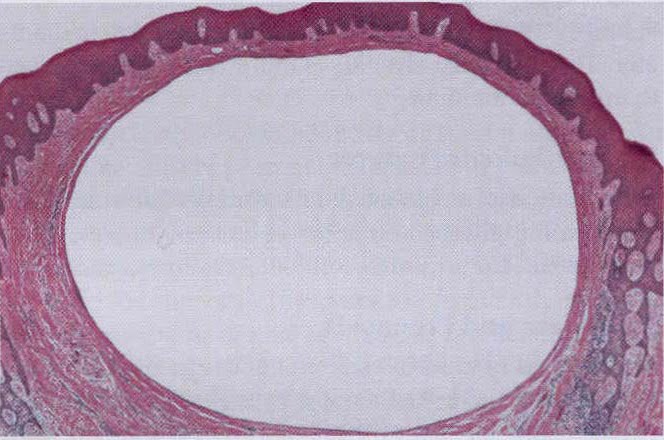

Гистологические изображения фолликулярной кисты яичника